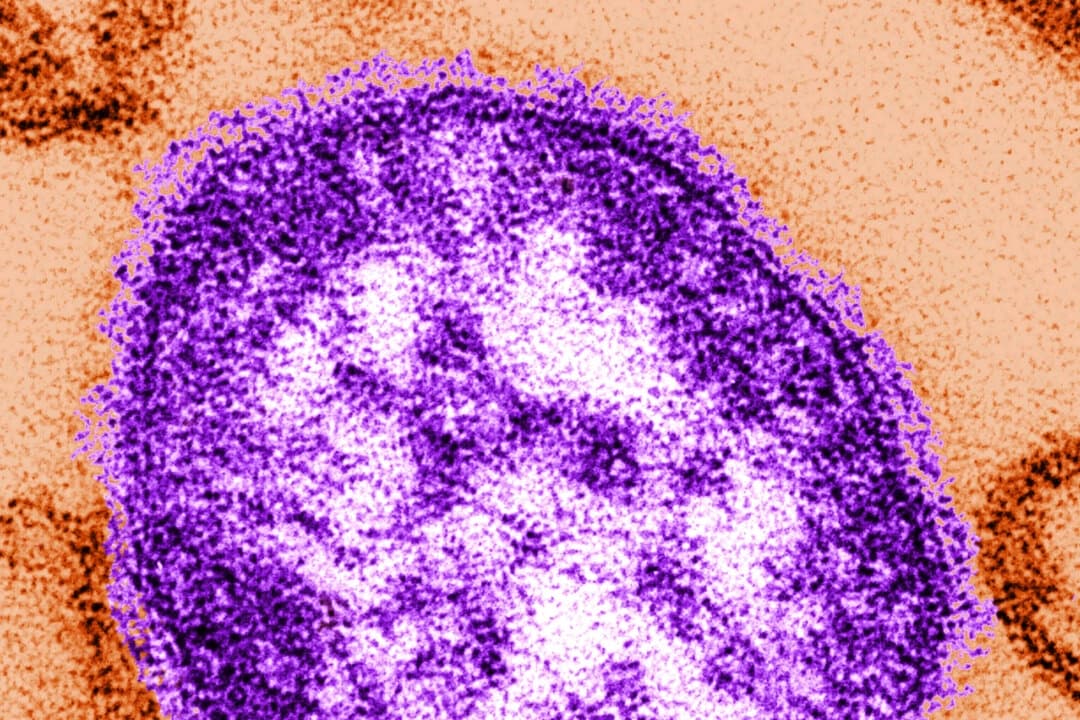

Brote de sarampión está "acelerando", según autoridades de Carolina del Sur

Más de 250 personas en cuarentena en EE. UU. por brote de sarampión, según autoridades

Muere adulto de Nuevo México infectado con sarampión, causa de la muerte no ha sido confirmada

El sarampión, un virus respiratorio, puede sobrevivir en el aire hasta dos horas y hasta nueve de cada diez personas susceptibles se infectarán si se exponen al virus